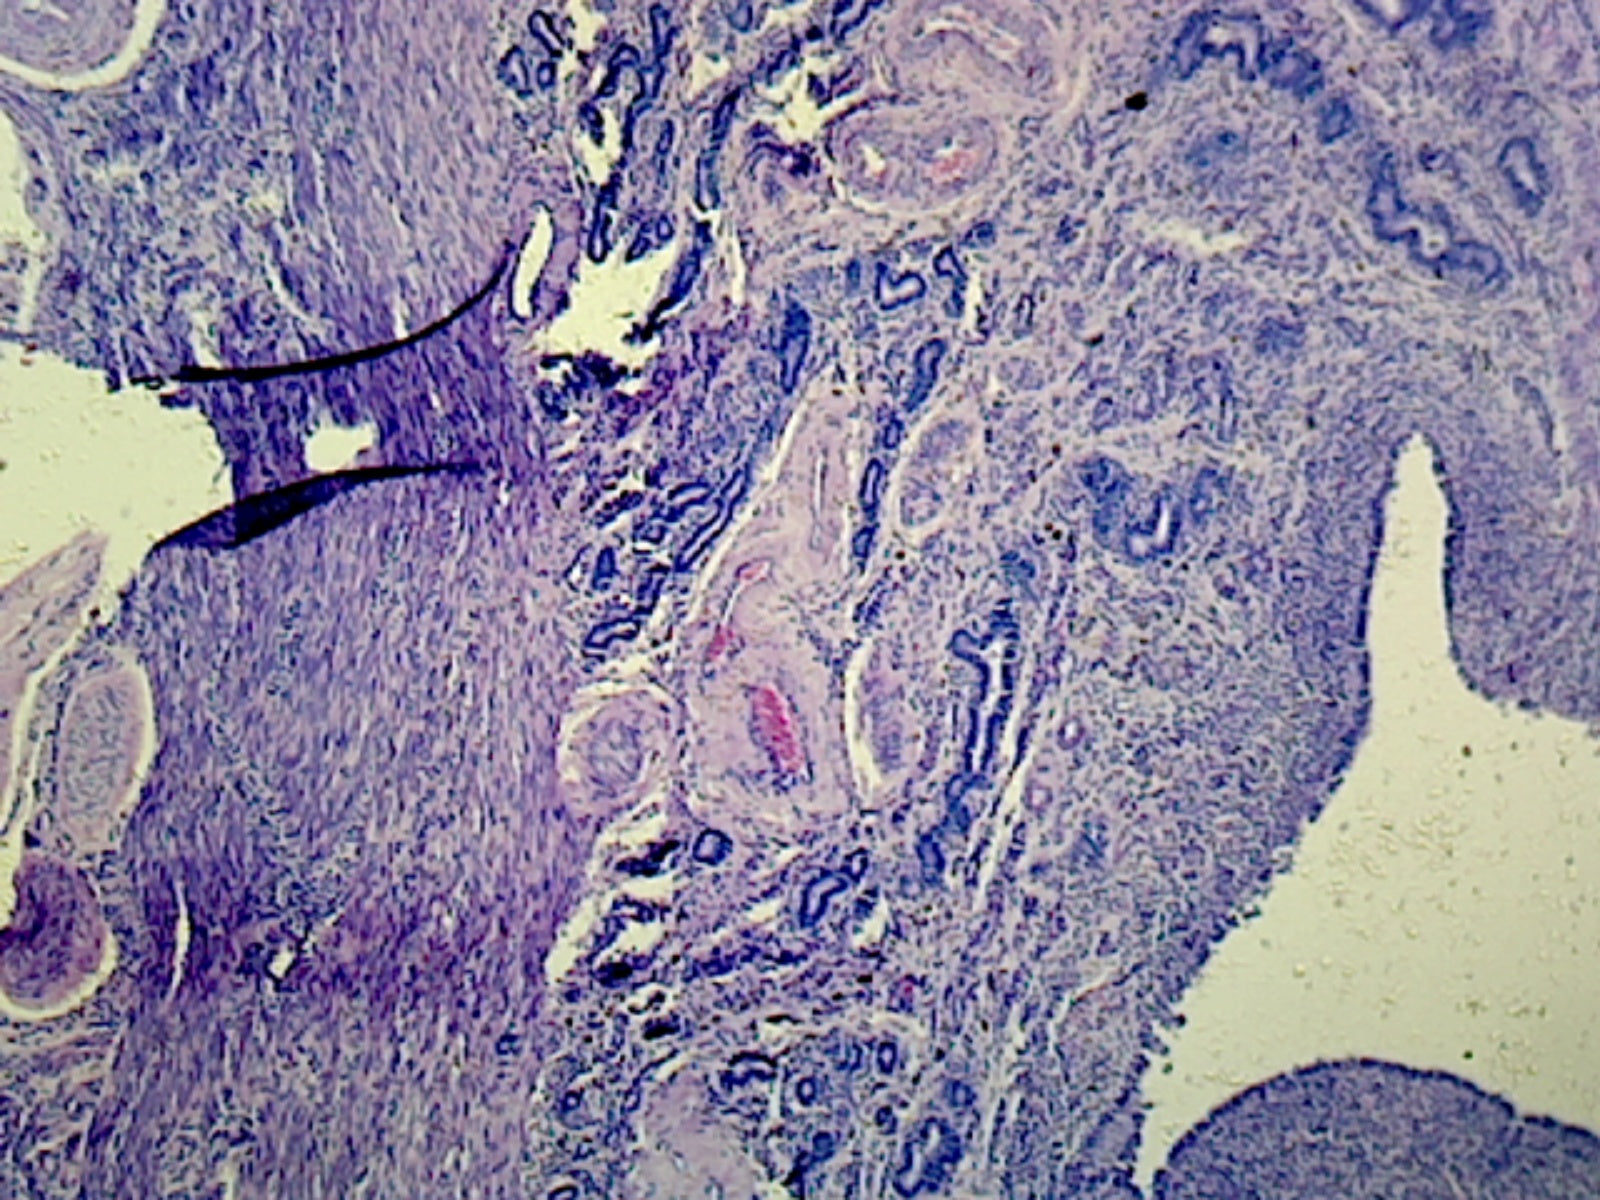

This slide is a section of a human uterus in its secretory phase. The secretory phase is also referred to as the progravid phase.